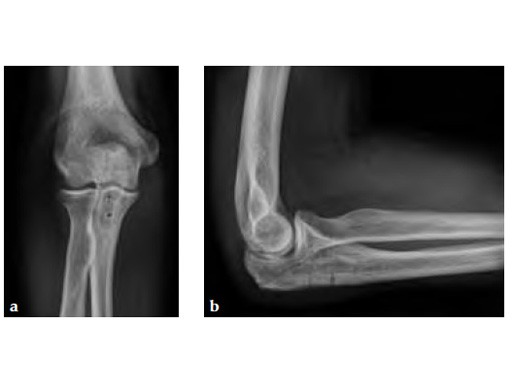

Fig 1ab Preoperative AP and lateral x-rays.